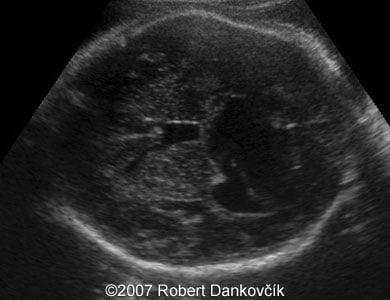

Images 1, 2: 2D sonography; 32 week of pregnancy; transverse planes through the fetal skull showing dilated third ventricle and dominant interhemispheric cyst extending to the right.

1

2